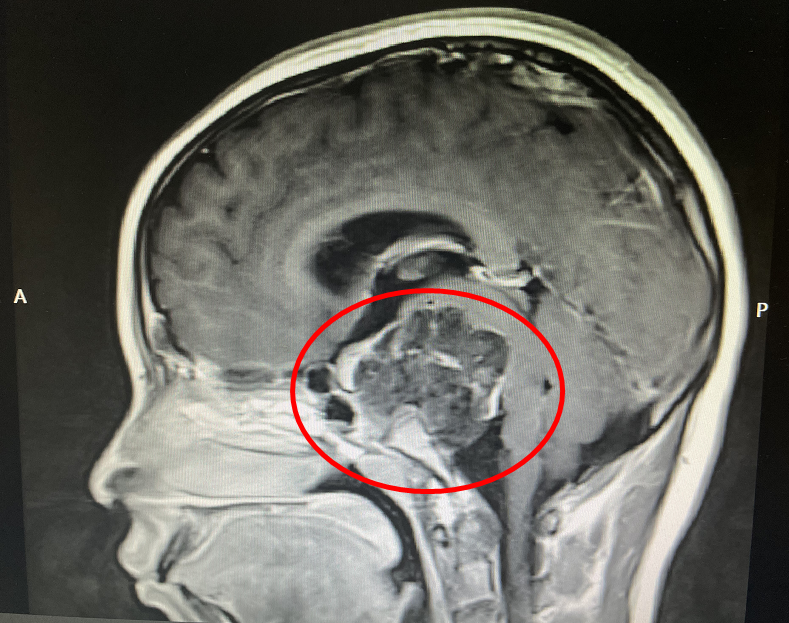

术前影像

在医院神经外科,由林志雄教授、翁超群主任带领的神经外科团队为小玉进行了系统的检查评估,发现孩子的肿瘤位于颅底,属于颅内脊索瘤,与重要的神经、血管及脑和脑干紧密相连;同时与国内多位颅底专家和神经内镜专家反复沟通,均认为通过手术切除肿瘤,难度高、风险大。但为了孩子的未来,专家团队决定放手一搏。

3日上午,小玉被推进手术室,历经6小时“奋战”,我院神经外科专家团队在双镜(脑室镜、显微镜)下切除了位于脑深处的巨大脊索瘤(5.5cm×5.1cm),手术过程顺利。术后,孩子清醒,神经功能没有出现新的损害。